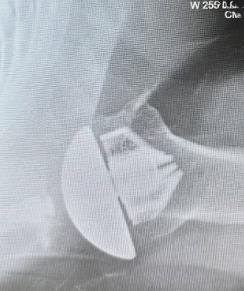

Summary The OsseoFit™ Stemless Shoulder System is indicated for anatomic total shoulder arthroplasty in patients where a bone-sparing, stemless solution is desired to maximize humeral fixation. It achieves this through OsseoTi® Porous Metal Technology and a site-specific fin design that creates a stable, biological press-fit while simplifying the surgical workflow with integrated suture holes. This system addresses a wide variety of patient anatomies using its versatile inlay and onlay size options. Indications Indications osteoarthritis indicated for anatomic total shoulder applications Contraindications local/systemic infection, sepsis, and osteomyelitis active local or systemic infection sepsis osteomyelitis inadequate humeral bone inadequate bone may lead to poor implant fixation large metaphyseal cysts may compromise stemless fixation irreparable cuff tear rotator cuff must be functionally reconstructable for anatomic total shoulder arthroplasty revision of any stemmed or stemless prothesis contraindicated for revision of any stemmed or stemless prosthesis Anatomy Osteology humeral head anatomic neck greater tuberosity lesser tuberosity bicipital groove metaphyseal cancellous bone Muscles deltoid forms the lateral border of the deltopectoral interval pectoralis major forms the medial border of the deltopectoral interval subscapularis released and repaired according to surgeon preference Ligaments glenohumeral capsule is released as needed to expose the humeral head and glenoid coracohumeral ligament contributes to rotator interval constraint superior, middle, and inferior glenohumeral ligaments contribute to anterior stability transverse humeral ligament overlies the bicipital groove Nerves axillary nerve courses inferior to the subscapularis and around the lateral humerus must be protected musculocutaneous nerve lies medial to the coracobrachialis and conjoint tendon suprascapular nerve is at risk with aggressive posterior-superior glenoid exposure Blood supply anterior and posterior humeral circumflex arteries arcuate artery is a terminal branch of the anterior humeral circumflex system suprascapular and circumflex scapular vessels Preoperative Planning X-rays A/P, scapular Y and axillary views evaluate bony anatomy, humeral head position, glenoid wear, deformity, and acquired bone loss use x-ray templates to estimate stemless humeral implant size assess whether an anatomic total shoulder reconstruction is appropriate CT assess bone quality and identify any humeral bone tissues use to assess bone quality and identify humeral bone issues that may affect implant selection evaluate metaphyseal bone stock, cysts, avascular necrosis, deformity, and cortical support Approach Extended deltopectoral anterior incision with an optional biceps tenodesis beginning immediately above the coracoid process and extending distally and laterally, following deltopectoral groove along the anterior border of the deltoid Technique Humeral head resection expose the humeral head and identify anatomic neck landmarks fixed-angle resection targets 135° inclination and 30° retroversion select left- or right-specific extramedullary resection guide align the guide post with the humeral shaft for fixed-angle resection align the 30° version rod with the forearm flexed at 90° place pins to define version and inclination and to stabilize the cutting surface resect the humeral head through the far side of the humeral head adjust the resection with the guide or calcar planer if needed assess bone quality with direct pressure perpendicular to the resected surface consider stemmed humeral fixation if cancellous bone is easily depressed or primary stability is questionable Humeral protection during glenoid preparation select the humeral resection cover that most closely fits the resected surface prepare the glenoid using the appropriate compatible glenoid technique remove the humeral resection cover before humeral sizing Humeral sizing place the humeral sizer onto the resection surface select the size intended to optimize cancellous bone fixation without violating the inner cortical rim orient the sizer so the bicipital groove bisects the superior and anterior fins insert the central Steinmann pin through the center of the sizer and through the lateral cortex avoid deep lateral cortical penetration to reduce risk to the axillary nerve place a lateral humeral retractor as needed to protect the axillary nerve confirm sizing after any additional planing Humeral bone preparation (boss reaming) ream until the boss reamer bottoms out on the resected surface ream over the central Steinmann pin with the boss reamer protect the lateral humerus and axillary nerve with a retractor remove the boss reamer while leaving the central Steinmann pin in place Humeral bone preparation (broaching) select the reference foot based on implant size select the broach that corresponds to the humeral sizer align the broach superior fin with the superior indicator line on the broach inserter slide the assembly over the central Steinmann pin until the broach contacts the resection surface remove the inserter-reference foot assembly and central Steinmann pin perform broach stability testing consider stemmed humeral fixation if the broach is unstable Humeral head trialing determine humeral head diameter and height using the humeral head sizing template or the resected humeral head seat the head trial assembly into the broach rotate the trial assembly with the hex driver to assess coverage of the resection surface confirm alignment with the anterior and posterior borders of the humeral resection increase offset if the head trial does not cover one side of the resection decrease offset if the head trial overhangs the resected bone reduce the joint and perform trial range of motion record the final offset letter or interval on the proximal humerus remove and disassemble the head trial assembly Implant insertion remove the broach with the slap hammer while maintaining an on-axis trajectory use the same reference foot size used for broach insertion select the implant size corresponding to the final broach and operative side slide the reference foot down until it uniformly contacts the resection surface confirm superior fin markings on reference foot, implant, and bone are aligned disengage the inserter-reference foot assembly with axial traction and slight rotational force as needed onlay implant center boss is slightly proud of the resection surface, with fin top surfaces flush inlay implant sits below the resection surface Humeral head implantation select the final humeral head implant matching the trial diameter and height use the offset letter or interval determined during trialing place the humeral head into the concave surface of the impactor base on a rigid sterile table impact the adapter into the humeral head with the disposable impactor using a mallet, strike the head impactor at least twice until the humeral head is flush with the resection visually confirm uniform seating consider implant subsidence and stemmed fixation if no pre-impaction gap is present Technical specifications Implant design anatomically shaped asymmetric anchor design designed to match natural asymmetric humeral anatomy designed to maximize cancellous bone fit and help avoid cortical impingement six-fin configuration with progressive tapered wedge design fins are designed for press-fit insertion each fin contains a fully porous window anterior suture holes are present for subscapularis repair Porous technology OsseoTi® Porous Metal Technology is used in the stemless implant porous architecture is designed to mimic human cancellous bone design incorporates a fully porous 3D printed OsseoTi® lattice within a titanium framework Technical specifications OsseoFit Onlay Anchor Implant Side Size Left 1, 2, 3, 4, 5 Right 1, 2, 3, 4, 5 OsseoFit Inlay Anchor Implant Side Size Left 1, 2, 3, 4, 5 Right 1, 2, 3, 4, 5 OsseoFit Humeral Head Adapter